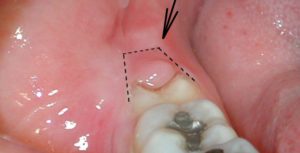

Воспаление капюшона возникает, когда зуб мудрости прорезывается через слизистую оболочку одним или несколькими буграми коронки. Т.е. получается ситуация, когда жевательная поверхность коронки зуба частично уже открыта, а оставшаяся часть – еще прикрыта слизистой оболочкой. Слизистая оболочка, нависающая над коронкой прорезывающегося зуба мудрости, называется Капюшоном (рис.1).

При прорезывании, восьмерка повреждает оболочку десны. Часть ее может быть открыта, а другая оставаться под нависающей над ней слизистой, которая называется капюшоном.

В образовавшееся пространство между капюшоном и зубом, попадают остатки пищи. Создаются благоприятные условия для размножения микробов. Воспалительный процесс называется перикоронитом.

Если зуб мудрости растет, на десне возникает складка, называется «капюшон». Туда могут попадать частички пищи, образуя хорошую среду для развития микробов.

Перикоронит – это один из главных факторов, почему болит прорезавшийся зуб мудрости. Под перикоронитом стоматологи подразумевают воспаление «капюшона» сверху зуба мудрости.

Как только третий моляр прорывается сквозь слизистую ротовой полости, для бактерий создаются наиболее благоприятные условия, позволяющие им размножаться. Ведь на десенной поверхности виднеется всего часть органа, остальное тело зуба находится еще под слизистой.

Над жевательной поверхностью моляра нависает так называемый капюшон, под которым и собираются болезнетворные микроорганизмы.

Воспалительный процесс в данном случае специалисты именуют, как перикоронит. Его основным признаком служит – болезненные ощущения в области, окружающих зуб, десенных тканей.